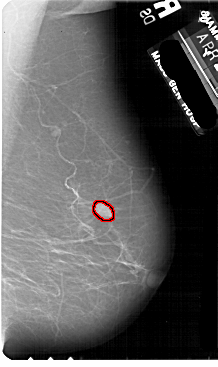

FILE: A_1881_1.RIGHT_MLO.OVERLAY

TOTAL_ABNORMALITIES 1

ABNORMALITY 1

LESION_TYPE MASS SHAPE LOBULATED MARGINS ILL_DEFINED

ASSESSMENT 4

SUBTLETY 4

PATHOLOGY BENIGN

TOTAL_OUTLINES 1

BOUNDARY